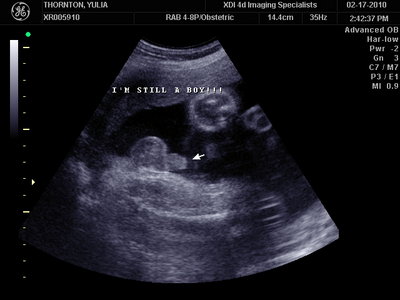

А это в 30 недель

MY BABY SONO!_20.JPG [ 94.63 КБ | Просмотров: 1038 ]

Sweetheart75 писал(а): Ну ладно, тогда и я нашего писюна покажу  Надеюсь, Джеффри на меня не обидится Вот это в 23 недели: (там оборудование переключалось из режима 3Д в обычный 2Д) Oоо, такое достоинство невозможно не заметить  А в 30 недель так вообще!